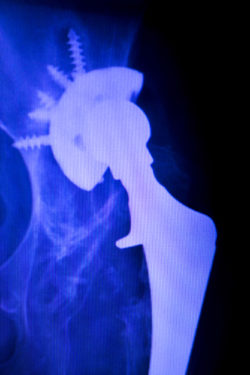

DePuy ASR hip implant recallDePuy, the makers of the DePuy ASR hip implant, has entered into a settlement to compensate patients who have experienced pain, suffering, need for revision surgery and other losses as a result of the failure of their implant.

The DePuy ASR metal hip is a metal-on-metal hip implant. Hip implants made from metal are thought to be more durable than their counterparts made with other materials. Some other hip implants are made with metal, but they have liners made of another material, such as ceramic or polyethylene, that prevent the metal parts from touching.

Because the metal parts in the DePuy ASR hip implant touch, a number of health complications can occur, and it is these complications that have given rise to reports that the hip implant is defective. When the pieces of the DePuy ASR metal hip implant touch, the friction of the metal pieces rubbing together causes the metal particles to slough off.